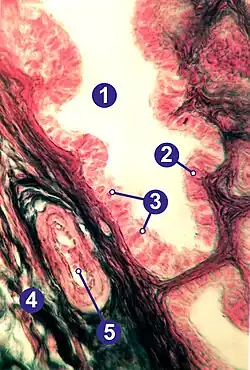

Die Mesosalpinx als ein seröser peritonealer Überzug bildet den oberen Rand des Ligamentum latum uteri. Die Muskelschicht (Myosalpinx) ist für die kontraktilen Bewegungen der Eileiter verantwortlich und aus einer äußeren Längsschicht und einer inneren zirkulären Schicht glatter Muskulatur aufgebaut.[1]

Die Schleimhaut (Endosalpinx oder Tunica mucosa) ist die innerste Schicht und weist Längsfalten auf. Das einschichtig hochprismatische Flimmerepithel enthält hauptsächlich sekretorische Zellen und zilientragende Epithelzellen, die im Verlauf des Eileiters und in Abhängigkeit vom Stadium des Sexualzyklus in jeweils unterschiedlichem Verhältnis verteilt sind.[1]